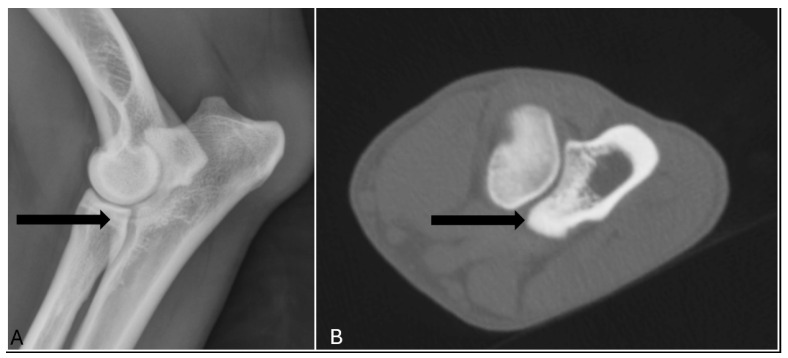

Diagnostic imaging is a crucial non-invasive tool for evaluating canine elbow joints, particularly for screening and treatment planning of medial coronoid disease (MCD). Radiography remains the most accessible and widely used screening modality, but its diagnostic accuracy varies significantly. Sensitivity values reported in previous studies vary depending on factors such as study population, imaging technique, and interpretation criteria. This study compared four measures (sensitivity, specificity, positive and negative predictive value) of radiography with a more advanced imaging method, computed tomography (CT), which provides more detailed images of bones. The results showed that radiography correctly identified 65% of the cases (17/26), while missing some of the affected joints. Furthermore, 7% of the healthy joints (29/398) were misdiagnosed as diseased, leading to a specificity of 93% (369/398). For a disease prevalence of 6% (26/424), the positive and negative predictive value of radiography were 37% (17/46) and 98% (369/378), respectively. Overall, when CT is available, it is the preferred technique for screening. In cases where it is not available, it is important to have an idea of the sensitivity and specificity, but also of the positive and negative predictive value, especially at low prevalences. These results help veterinarians make better decisions when screening for elbow problems in dogs.